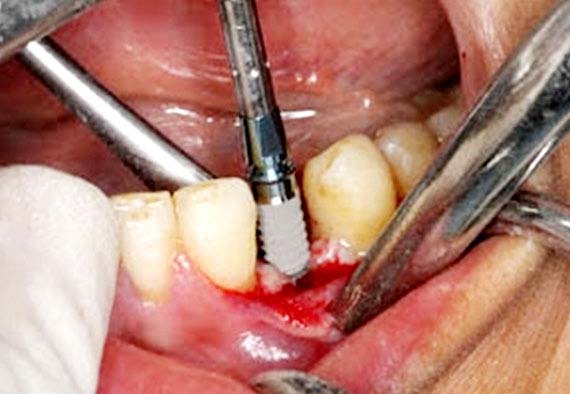

Peizosurgery

It is a relatively new modality for osteotomy and osteoplasty that utilizes ultrasonic vibrations for bone cutting. The advantages are minimum tissue damage, better healing and precise control of working tip. The peizosurgical unit is routinely used in various bone modulation surgeries in our college.